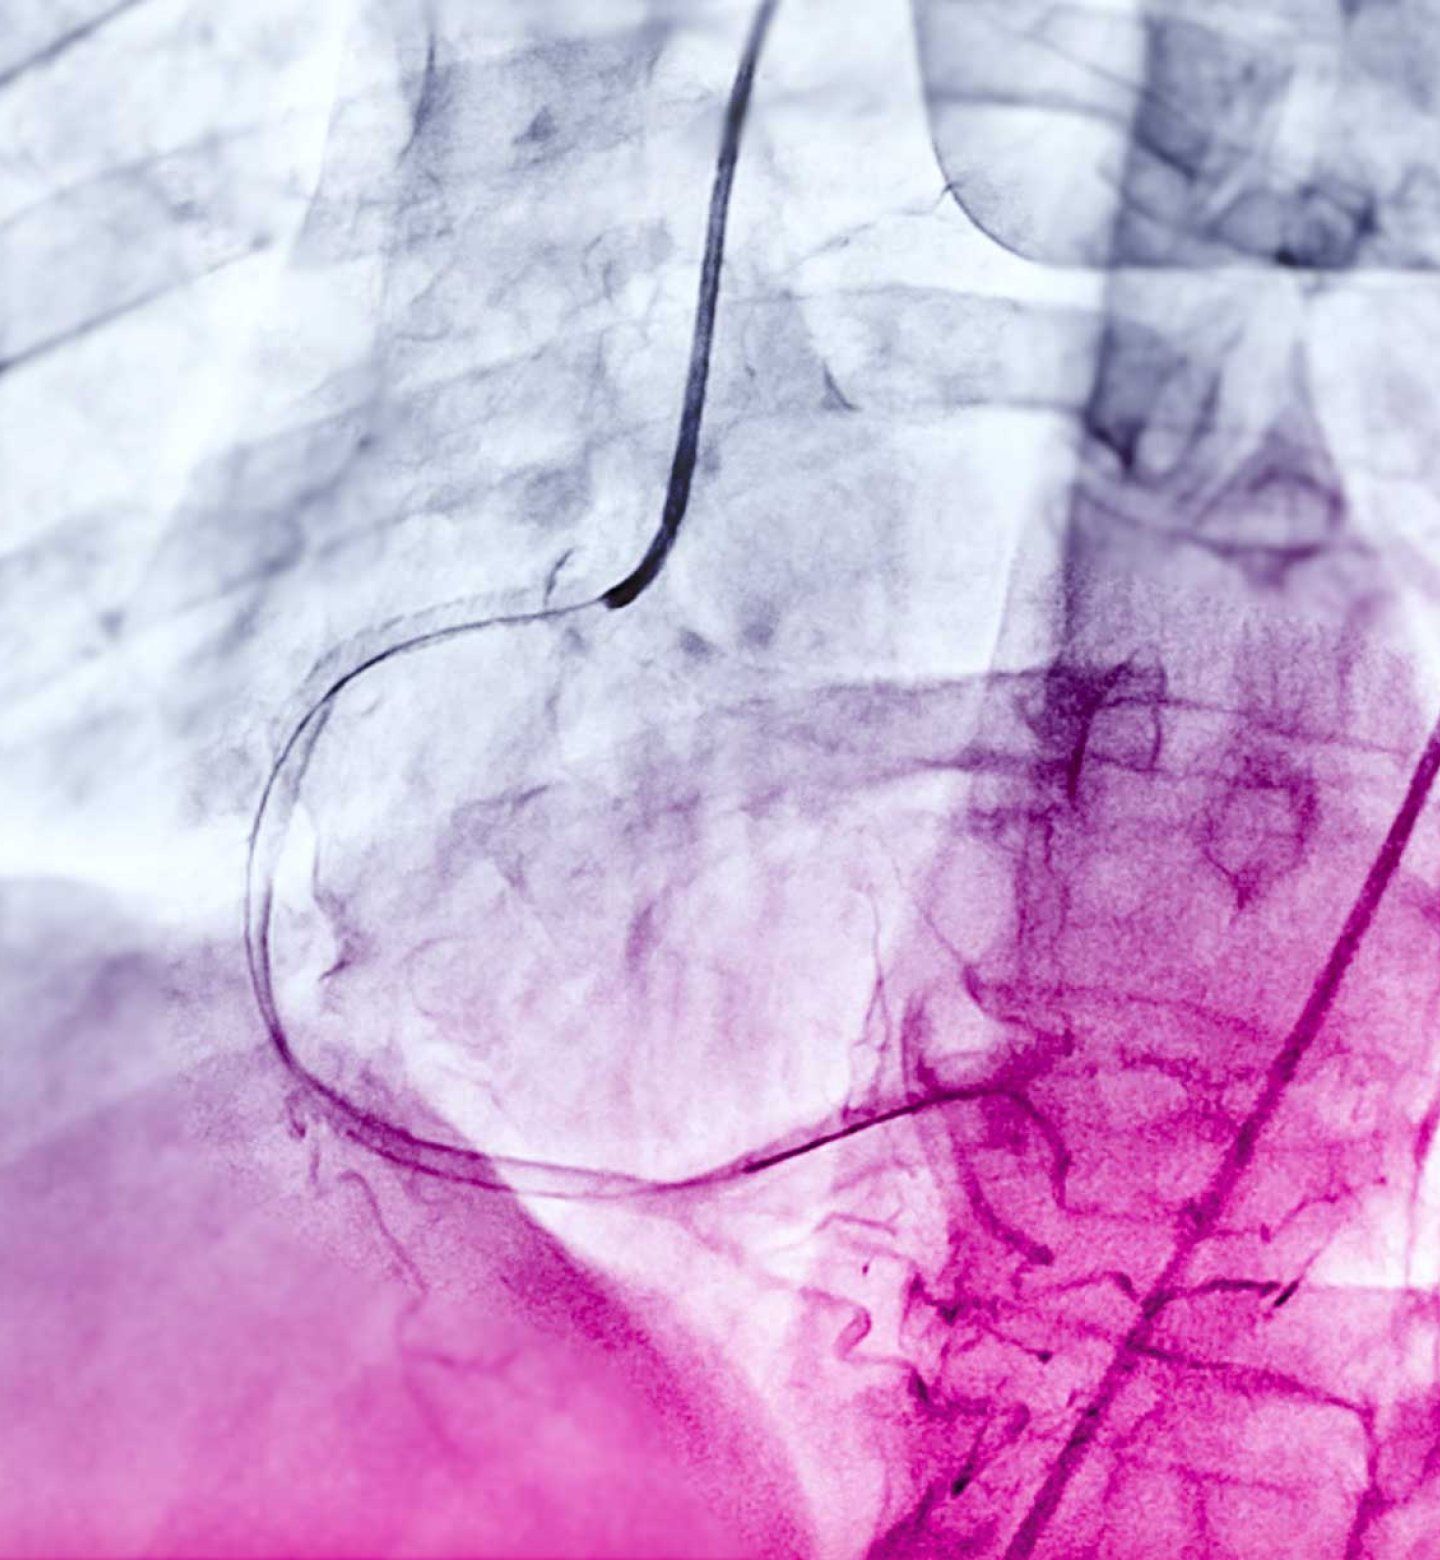

Angiograms, much like this above, could one day be used to diagnose more serious cardiac issues without further risky testing.

Physicians commonly use a test called a coronary angiogram to diagnose the condition. As part of angiograms, physicians inject a special dye into the main vessels that feed the heart to see how blood flows using x-rays. Angiograms much like this could one day be used to diagnose more serious cardiac issues without further risky testing.

The heart’s left ventricle is the heart’s main pumping chamber but coronary artery disease can damage it. Patients with suspected severe coronary artery disease undergo angiograms, but may also need additional testing with even more dye that can harm the kidneys.

New research by UCSF cardiologist Geoff Tison, M.D., MPH, and team is among the first to successfully use machine learning to estimate how well the left ventricle is pumping by analyzing standard angiogram videos that are already obtained from the coronary angiogram procedure. This provides information about the heart’s function without requiring additional procedures or risk. The research could eventually give physicians and patients a quicker and less dangerous way to diagnose damage to the left ventricle.

Tison and team trained a type of AI model called a deep neural network on anonymized angiogram videos recorded at UCSF. Deep neural networks are able to learn complex patterns in data such as images and videos, some of which are not readily apparent to humans.

The team’s model, dubbed CathEF, accurately predicted how well the left ventricle pumped when researchers compared the results to measurements of pump function taken from ultrasound. CathEF performed just as well when the team later tested it outside the lab, in a Canadian hospital.

“CathEF offers a novel approach that leverages data routinely collected during every angiogram to provide information that is not currently available to clinicians,” said Tison. “Our model effectively expands the utility of medical data with AI with real-time information to inform clinical decision-making.”